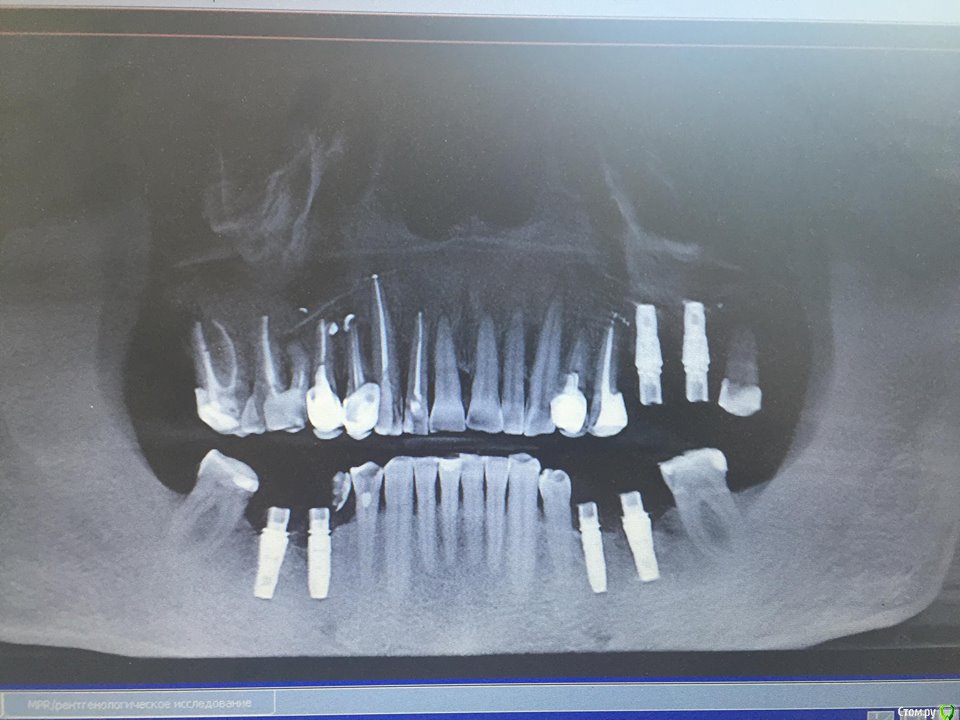

лемурка Опубликовано 29 августа, 2018 Поделиться Опубликовано 29 августа, 2018 Здравствуйте, уважаемые профессионалы! Суть проблемы:Мужу 63 года. Два года назад ему были установлены 6 имплантатов Astra с субгингивальным погружением. Хирург не посчитал необходимым наращивание костной ткани, хотя 6 зуб нижней челюсти справа отсутствовал более 30 лет.Сейчас, когда пришло время установки постоянных коронок, оказалось, что имплантаты на нижней челюсти установлены плохо, торчат над костной тканью, особенно на месте 5 зуба, находящегося рядом с 6 ранее отсутствующим. Шаблоны не применялись. Есть ощущение, что 5 имплантат не совсем в ряду, смещен внутрь. Десны в местах установки 5,6 имплантатов с обеих сторон нижней челюсти впалые и более темного цвета. Цвет десен в месте установки имплантатов на верхней челюсти нормальный, и эффект впалой десны отсутствует. Болей в области установленных имплантатов нет. Предлагаемые варианты решения сложившейся ситуации на сегодняшний момент: Первое мнение:1) Хирург, сделавший имплантацию, признает проблему торчащих имплантов, но предлагает ограничиться пластикой десен 5, 6 зубов с обеих сторон нижней челюсти.Объясняет это тем, что с имплантатами ничего плохого не произойдет, из костной ткани они не выпадут, несмотря на то, что не полностью туда погружены (5 имплантат торчит над костной тканью якобы на 1 мм). А операция по удалению и установке новых - травматичная, с возможностью разных осложнений, как, собственно, и любая операция. Удалять данные имплантаты очень сложно. Предлагает вскрыть десны, обточить инструментом торчащие из костной ткани части имплантатов для удаления остатков прилипших тканей и сверху сделать пластику десен. Это, по его мнению, должно решить проблему попадания пищи и невозможности нормальной гигиены.Из-под десен под имплантатами нижней челюсти при надавливании инструментом появляется в небольшом количестве белое содержимое. Врач характеризует эту субстанцию как смесь десневой жидкости с остатками попадающей пищи. После пластики деснен эта проблема якобы должна исчезнуть. Второе мнение:2) Есть мнение другого врача, который считает, что с костной тканью проблем нет, наращивание ее не требуется (собственно, как и первый хирург), но надо заменить все (!) 4 нижних имплантата на новые с субкрестальным погружением другой фирмы, штрауман, также добавив пластику десен с двух сторон. Врач объясняет наличие выделяемой белой субстанции неким воспалительным процессом не в костной ткани, но тем не менее также требующим кардинального решения удаления имплантатов. Вопрос:Опуская материальную сторону, хотелось бы услышать ваше компетентное мнение по сути проблемы. Как поступить правильно? В принципе готовы далее заниматься исследованием ситуации и посетить еще врачей, но, как видите, уж очень разные подходы к решению проблемы. Неспециалисту сложно принять взвешенное решение, поэтому хочется услышать максимальное количество согласий с одним из мнений или услышать ваше. Возможно, есть еще какие-либо варианты ? Я в шоке, если честно. Спасибо. Р.S. Хирург - имплантолог выбирался долго, и был не из дешевых.(( Привожу снимки августа 2016-ого года (сразу после установки) и 2018-ого года. Ссылка на комментарий

лемурка Опубликовано 7 сентября, 2018 Автор Поделиться Опубликовано 7 сентября, 2018 (изменено) +11мм не проблема.Nazim, это врач говорит, что выступает на 1мм. На снимках длина всего имплантата равна 11мм ( все четыре имплантата имеют такую длину), судя по паспортам, нам переданным. Может, там и 2 мм...Ситуация на данный момент - врач, установивший имплантаты, настоятельно советует пересадку десны ( для начала с правой стороны) и то, что меня смущает больше всего - шлифовку выступающих над костной тканью имплантатов.К сожалению, никто из врачей не написал, насколько эта процедура правильна, распространена в такой ситуации и решает проблему скапливания микробов вокруг имплантата в зоне, выступающей над костной тканью. Есть смысл ее делать? Врач утверждает, что десна не сможет приклеиться к имплантату, и поэтому необходимо сделать эту шлифовку, чтобы уменьшить существование в этой области микробов(( Кто-нибудь практикует такую шлифовку? Имеет смысл ее делать? Насколько это реально отшлифовать эту часть, если она составляет 1-2 мм? После такой некачественной установки имплантатов не очень доверяю этому врачу(( Изменено 7 сентября, 2018 пользователем лемурка Ссылка на комментарий